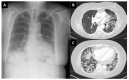

Results: In total, 15 cases of new onset myositis (11 polymyositis/necrotizing/overlap myositis; 4 dermatomyositis) were identified in the Yorkshire region of approximately 5.6 million people, between February 2021 and April 2022 (10 females/5 men; mean age was 66.1 years; range 37-83). New onset disease occurred after first vaccination (5 cases), second vaccination (7 cases) or after the third dose (3 cases), which was often a different vaccine. Of the cases, 6 had systemic complications including skin (3 cases), lung (3 cases), heart (2 cases) and 10/15 had myositis associated autoantibodies. All but 1 case had good therapy responses. Adverse event following immunization (AEFI) could not be explained based on the underlying disease/co-morbidities.